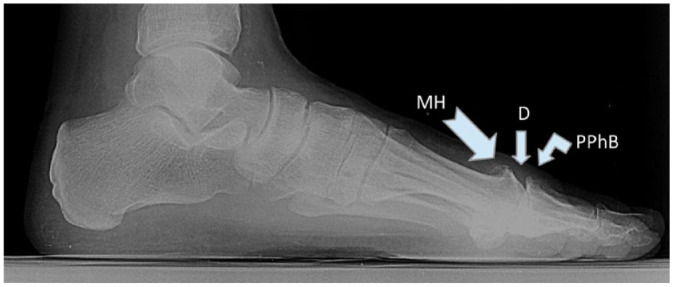

我们报告了第一例通过交联透明质酸(HA)21 毫克/毫升与甘露醇(Desirial Plus)的关节内浸润成功治疗一名老年硬下疳患者的病例,并回顾了以往应用于硬下疳HA浸润治疗的不同成分的文献。一名 77 岁的女性患者,左足第一跖趾关节中度单侧疼痛,已持续 6 个月,活动僵硬,属于 Coughlin 和 Shurnas 提出的分类中的 2 级。该研究的目的是进行一项试点测试,以(a)评估关节内浸润的正确技术,以及(b)对一名被诊断为拇指外翻僵直症的自愿患者使用含甘露醇的 21 毫克/毫升商业交联 HA。对第一跖趾关节进行单次交联医管局浸润,用量为 1 毫升。第一跖趾关节的负重背屈角、非负重背屈角和非负重跖屈角分别从注射前的15°、20°和10°改善到注射后14天的45°、52°和22°。此外,这些改善一直持续到最后的随访(400 天)。根据视觉模拟量表,疼痛强度从注射前的 10 分中的 7 分,到注射后 14 天的 10 分中的 4 分,再到注射后 60 天的 10 分中的 1 分,均有所改善。含有甘露醇的 21 毫克/毫升交联 HA 可改善接受试点测试的僵硬拇指患者的症状、第一跖趾关节的关节活动度和生活质量。这些效果已维持了 14 个多月。

We report a first case of hallux rigidus successfully treated in an elderly patient by intra-articular infiltration of cross-linked hyaluronic acid (HA) 21 mg/mL with mannitol (Desirial Plus) and review the previous literature on the different compositions of HA infiltrative treatment applied to hallux rigidus. A 77-year-old female patient with moderate unilateral pain of 6 months of evolution and stiffness of the movement of the first metatarsophalangeal joint of the left foot, corresponding to grade 2 of the classification proposed by Coughlin and Shurnas. The objective of the study was to perform a pilot test to (a) evaluate the correct technique of intra-articular infiltration as well as (b) the use of a commercial cross-linked HA 21 mg/mL with mannitol, to a voluntary patient diagnosed with hallux rigidus. A single cross-linked HA infiltration is applied to the first metatarsophalangeal joint with an administered amount of 1 mL. The loaded dorsiflexion, the unloaded dorsiflexion, and the unloaded plantarflexion angles of the first metatarsophalangeal joint improved from 15°, 20°, and 10°, respectively, before injection to 45°, 52°, and 22°, respectively, at 14 days after injection. Moreover, these improvements maintained until the final follow-up (400 days). The intensity of pain, according to the visual analog scale, improved from 7 of 10 before the injection, passing through 4 of 10 at 14 days after the injection, to 1 of 10 at 60 days after the injection. Cross-linked HA 21 mg/mL with mannitol improves symptomatology, joint mobility of the first metatarsophalangeal joint, and quality of life in the patient with stiff hallux submitted to the pilot test. These effects have been maintained for more than 14 months.